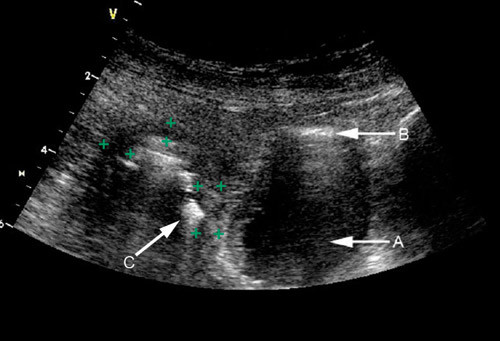

Danning av fistler er en hyppig komplikasjon ved Crohns sykdom. Fistlene utgår fra tarmveggen og kommuniserer med andre tarmsegmenter, mesenteriet eller andre strukturer som urinblære, vagina eller perineum (12). Ved ultrasonografi ses fistler ofte som avlange hypoekkogene områder. Små, hyperekkogene flekker kan noen ganger ses innenfor slike områder på grunn av innhold av luft, debris eller avføring i fistelen (9, 20). I noen tilfeller kan man sannsynliggjøre fisteldanning til tross for at man på ultralyd ikke ser fistelen. Dette gjelder spesielt for enterovesikale fistler (fig 4).